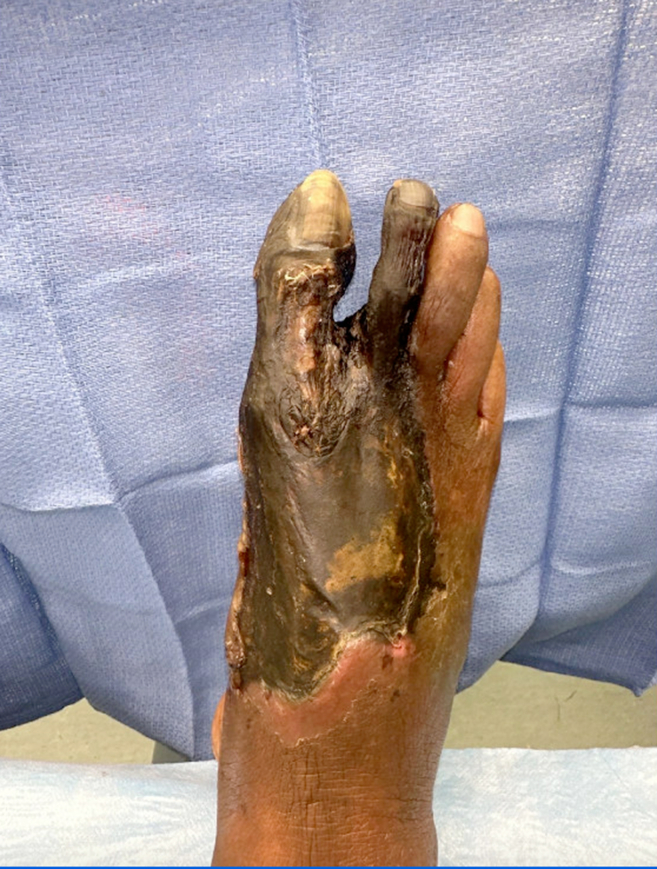

Clinical Images in Emergency Medicine: Man With Foot Pain and Indifference.

Alex Y Koo, Susan R O'Mara